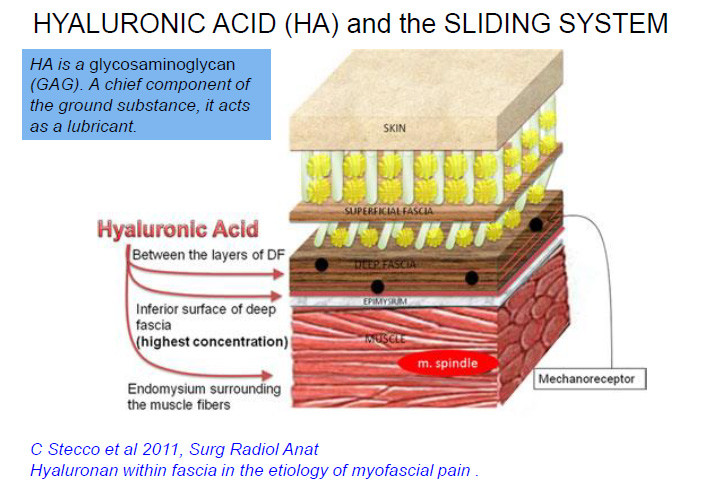

근막 리프팅 시술을 통해 혈액 순환을 개선합니다.